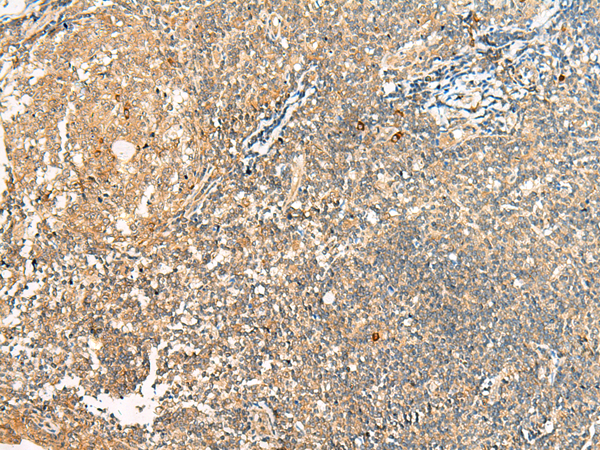

分类: 科研抗体货号: P13553别名: HBP; HEBP应用: WB,IHC反应种属: Human